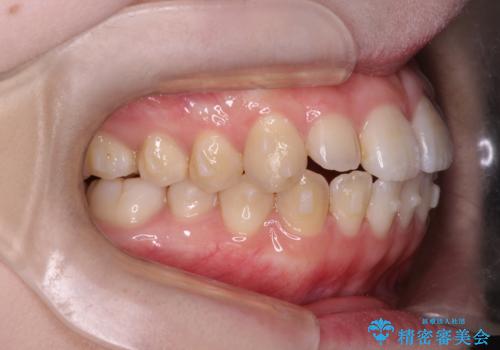

前歯がガタガタ・噛み切りにくい インビザラインによる歯を抜かない矯正

前歯にがたつきがあり、上下の歯が咬み合っていない状態でした。

歯列の横幅をひろげるのと、歯と歯の間をわずかに削ることにより、前歯のがたつきと、開咬を改善しました。